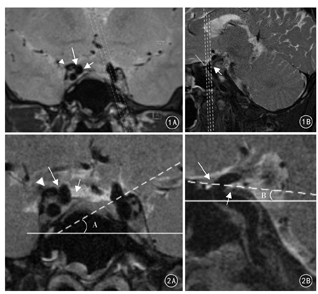

HR-DIR-T2WI扫描范围:以颈内动脉床突段为中心,DDR内缘至DDR外缘。扫描方法:(1)DDR矢状位扫描。冠状位3D-SPACE-T2WI显示DDR内侧、外侧,旋转定位线使之垂直于内外侧隔的连线,并使3层定位线的中间层位于DDR中心点位置(图1A)。(2)DDR冠状位扫描:矢状位HR-DIR-T2WI显示旋转定位线垂直于DDR前后缘连线平面扫描,并使3层定位线的中间层面位于DDR中心点位置(图1B)。

在3D-SPACE-T2WI和HR-DIR-T2WI序列上进行比较测量。外内侧平面倾斜角的测量:冠状位选取颈内动脉床突段穿隔层面,以颅底为标志做水平线,DDR外缘和内缘穿隔点的连线即为外内侧平面,外内侧平面与水平线的夹角即为外内侧平面倾斜角(图2A)。前后侧平面倾斜角的测量:矢状位选取颈内动脉床突段穿隔层面,以颅底为标志做水平线,DDR前缘和后缘穿隔点连线即为前后侧平面,前后侧平面与水平线的夹角即为前后侧平面倾斜角(图2B)。需分别测量DDR右侧及左侧的外内侧平面倾斜角及前后侧平面倾斜角,并进行比较。

在3D-SPACE-T2WI和HR-DIR-T2WI序列上,20例(40侧)志愿者中冠状位DDR外内侧平面均呈外高内低型(图2A);矢状位DDR前后侧平面36侧呈前高后低型(图2B),4侧呈前低后高型。HR-DIR-T2WI序列显示DDR与颈内动脉边缘更为锐利,显示更多细节,从而使测量更加准确;3D-SPACE-T2WI可多平面、多角度全面观察DDR结构。